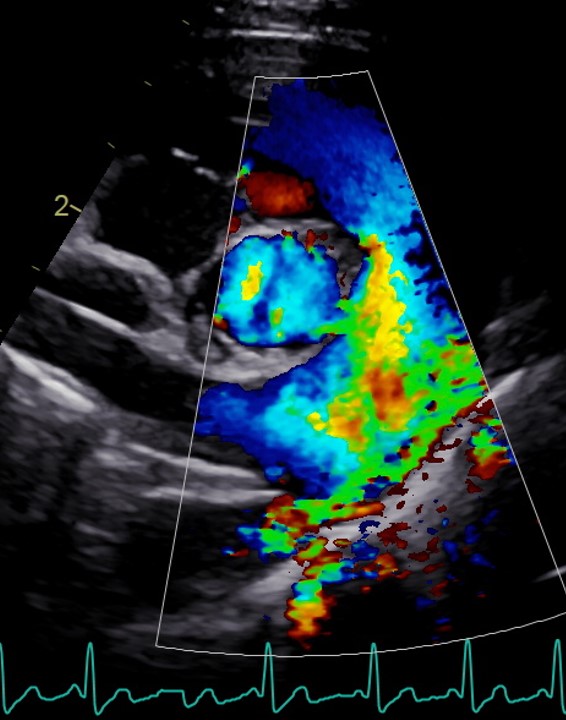

Chaque participant présente un cas clinique (ou plusieurs images) pour revoir le protocole d'échocardiographie et échanger :

Le formateur proposera également quelques coupes échocardiographique non conventionnelles et quelques cas “pièges” pour approfondir l'analyse et la réflexion.